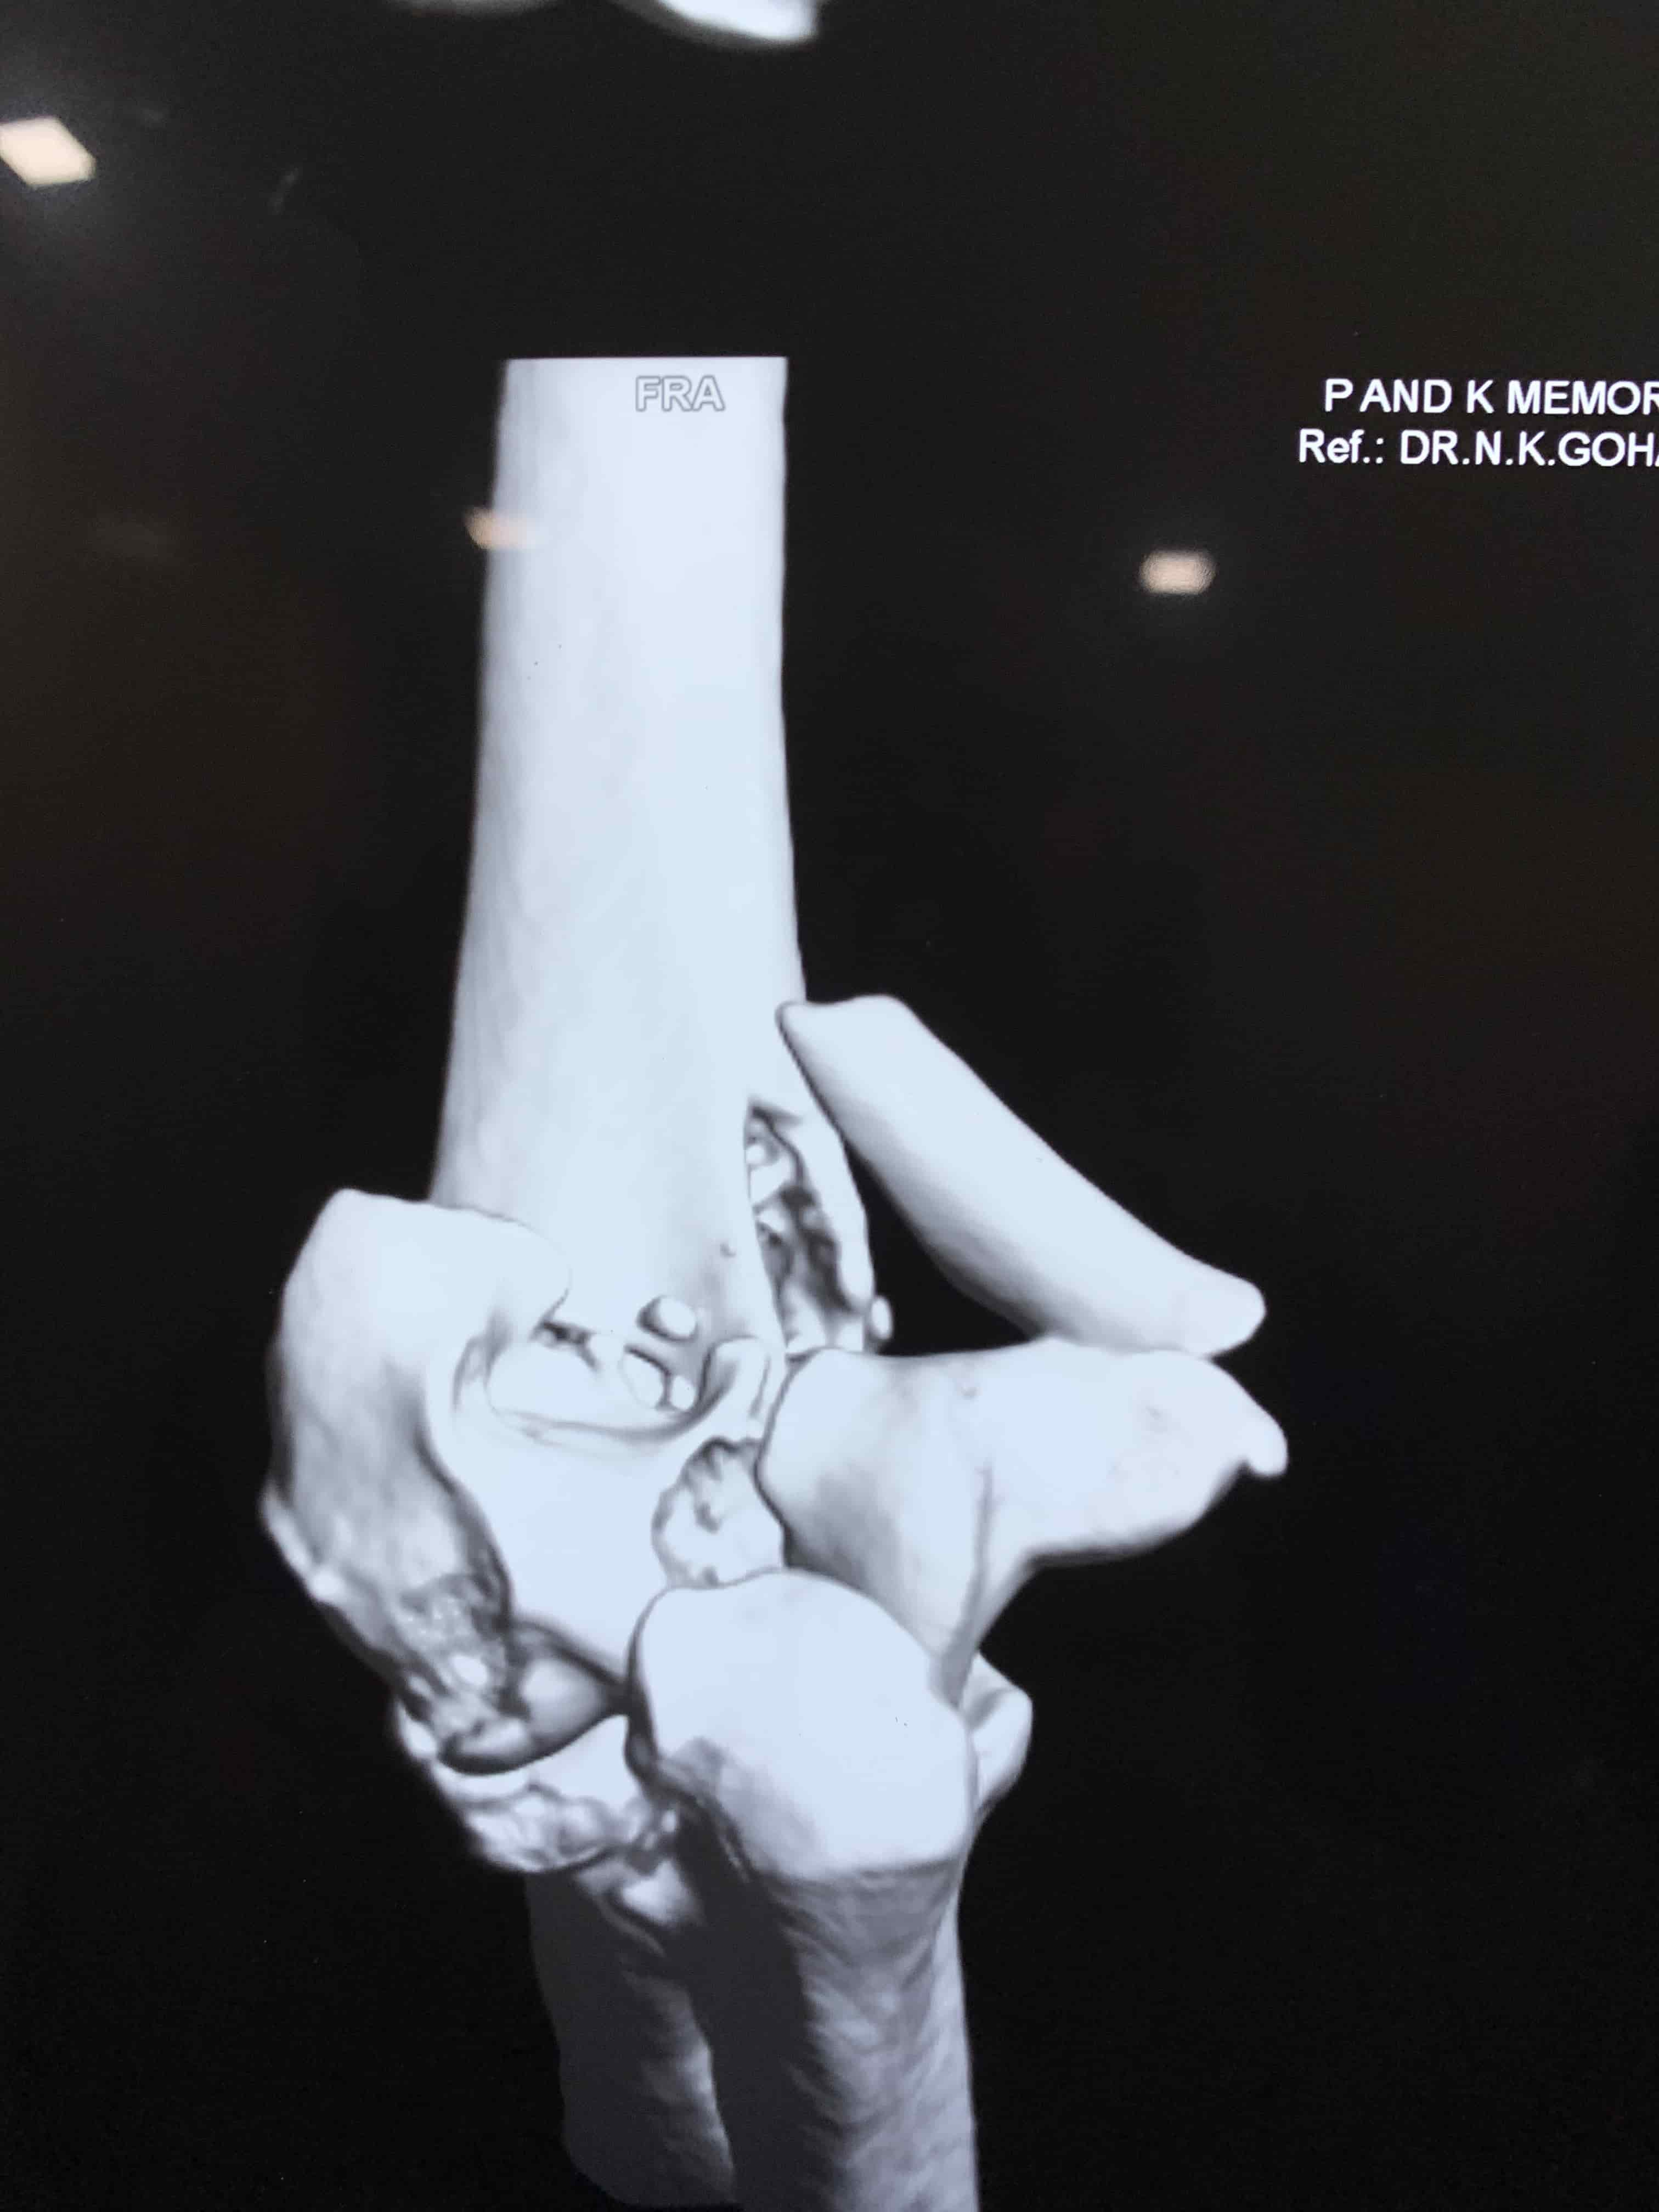

Complex Distal Humerus Comminuted Fracture

Complex Distal Humerus Comminuted Fracture

Complex Distal Humerus Comminuted Fracture

Complex Distal Humerus Comminuted Fracture

Complex Distal Humerus Comminuted Fracture

Complex Distal Humerus Comminuted Fracture

Complex Distal Humerus Comminuted Fracture

Complex Distal Humerus Comminuted Fracture

Complex Distal Humerus Comminuted Fracture

Complex Distal Humerus Comminuted Fracture

Complex Distal Humerus Comminuted Fracture

Complex Distal Humerus Comminuted Fracture

Complex Distal Humerus Comminuted Fracture

Complex Distal Humerus Comminuted Fracture